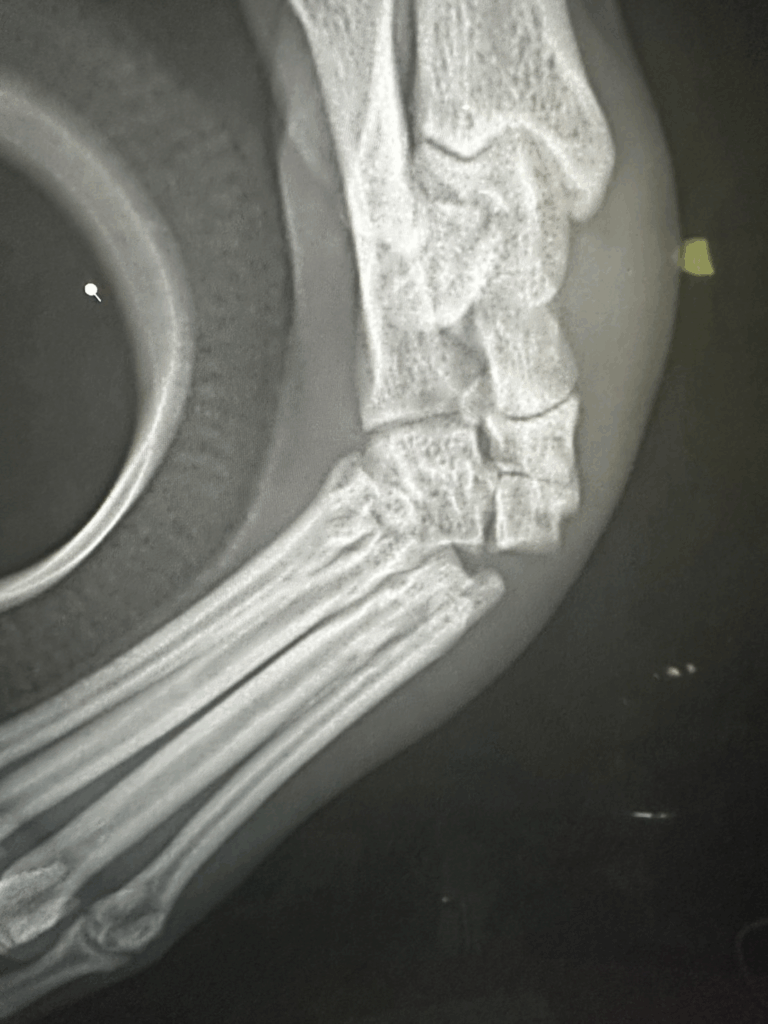

中足骨間脱臼の診断は、通常のレントゲン撮影では見逃されることも多い疾患です。

骨自体が折れていない場合、靱帯損傷や微妙な骨配列のズレを見抜くには、

整形外科に特化した知識と撮影技術、そして経験が必要です。

- 高精度レントゲンによる角度・位置の評価